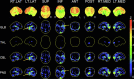

Fig. 3

Fluorine – 18- fluorodeoxyglucose positron-emission tomography / computed tomography (FDG PET/CT) 3D stereotactic surface projection and normal database comparison (Neurostat): Localized hypometabolism in the left temporal lobe (arrows). Visual cortex hypometabolism related to general anaesthesia.